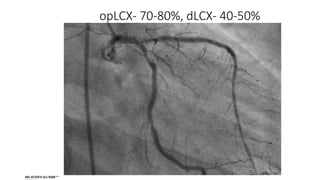

opLCX- 70-80%, dLCX- 40-50%

opLCX- 70-80%